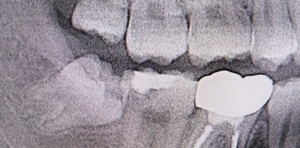

After(下親知らずの抜歯後) 横に生えた状態で埋まっている親知らずの抜歯後 虫歯がある親知らずの抜歯後 抜歯後の骨の状態のレントゲン像

1年後、取り除いた親知らず周囲の骨がしっかり再生したことを確認しました。